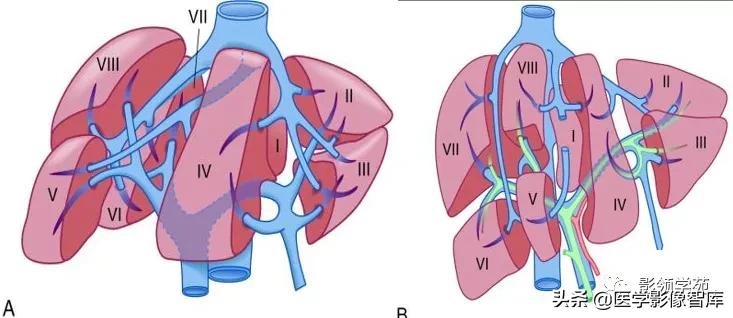

3支主肝静脉将肝分隔成4个部分。

左、中、右3支主肝静脉走行区所形成的纵形切面(称为肝静脉裂)将肝分隔成4个部分,称为四个扇区。

每个扇区又被门静脉左、右支的水平切面分成上下2段。

4个扇区不包括尾状叶。

尾状叶编为Ⅰ段,它是一个自主段,因它不依赖于4个肝门静脉蒂和3支主肝静脉。

尾状叶同时接受来自左右肝门静脉和肝动脉的分支供血,其静脉血经肝小静脉直接回流入下腔静脉。

肝脏被正中裂分左、右半肝,左、右半肝又分为四部。

左半肝分内、外两叶,右半肝分前、后两叶

门静脉左、右支充当横裂,将四部又分为八段。

前面观

下面观

记忆:

第一肝门以上顺时针:7 8 4 2

第一肝门以下顺时针:6 5 4 3

整个的分段,顺时针走向 2、3、4、5、6、7、8